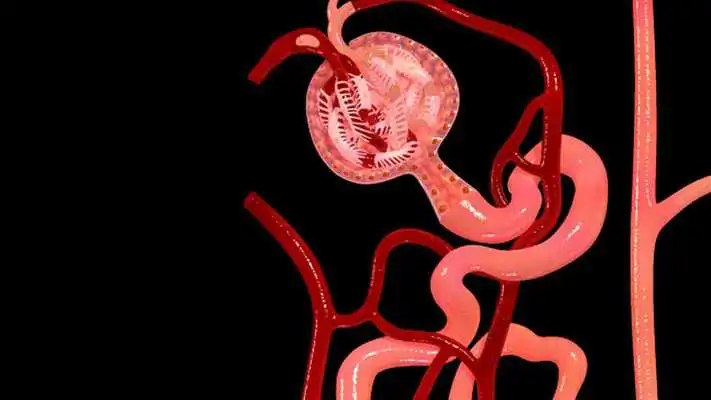

Nephron Blood Vessels 3D

Nephron Blood Vessels 3D

DESCRIPTION

Play this online game named Nephron Blood Vessels 3D.

Nephron Blood Vessels 3D - Key Features :1) You can Zoom and Rotate the 3d model.

2) Take apart to understand the anatomy better.

3) Each layer or object can be made Glassy to see through.

4) Label or Title every object or layer.

5) Analyse feature allows educators for show special focus on a specific part.

6) Snap feature allow you to save the image of the 3D or augmented reality model. This image can be used for your next project or learning. Share or upload or print the images to showcase it to your friends.

7) Pen tool allows teachers to draw or pin specific parts of the Model.

8) The AR button allows you to bring the model from virtual world to real life situation by placing the camera on a marker.